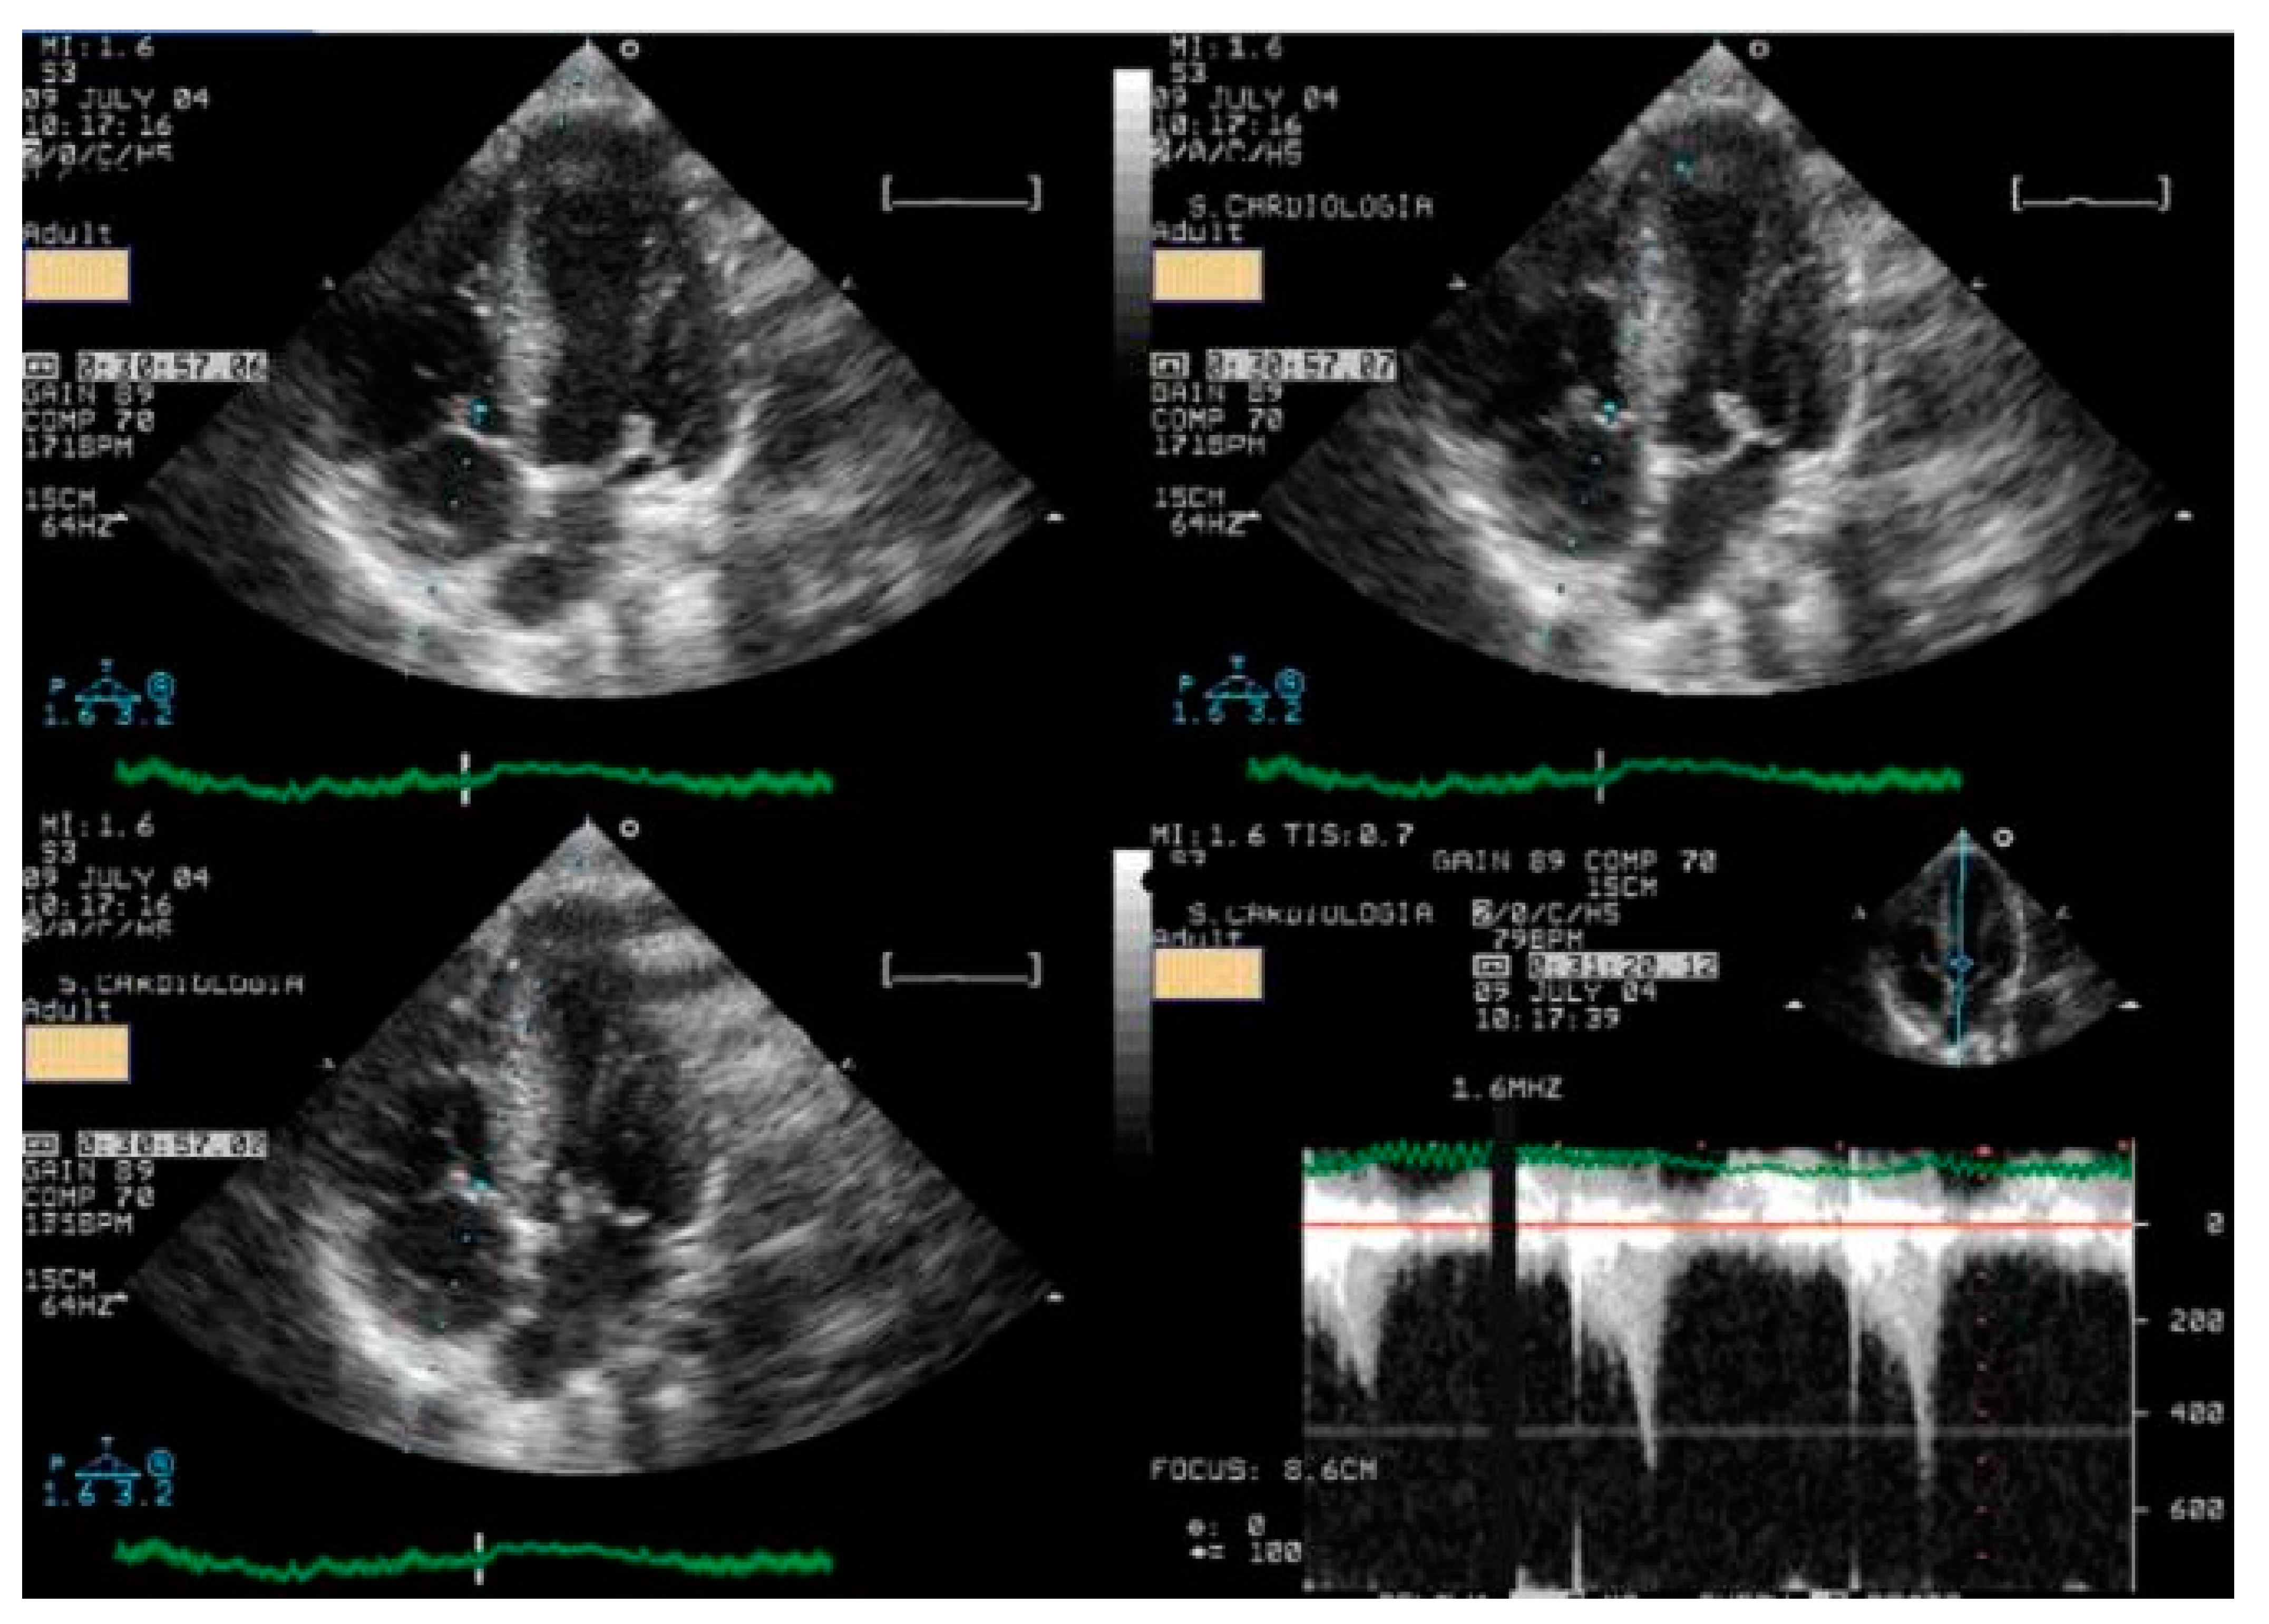

We read with interest the excellent review manuscript from Huang, S.-W. and Liu, Y.-K. [1], which describes that pediatric chest pain is a common chief complaint in the emergency department. Not surprisingly, children with chest pain are usually brought to the emergency department by their parents out of fear of heart disease. However, chest pain in the pediatric population is generally a benign disease. In this review, we have identified musculoskeletal pain as the most prevalent etiology of chest pain in the pediatric population, accounting for 38.7–86.3% of cases, followed by pulmonary (1.8–12.8%), gastrointestinal (0.3–9.3%), psychogenic (5.1–83.6%), and cardiac chest pain (0.3–8.0%). Various diagnostic procedures for cardiac chest pain are commonly used in the emergency department, including electrocardiogram (ECG), chest radiography, cardiac troponin examination, and echocardiography. However, these examinations demonstrate limited sensitivity in identifying cardiac etiologies, with sensitivities ranging from 0 to 17.8% for ECG and 11.0 to 17.2% for chest radiography. To avoid the overuse of these diagnostic tools, a well-designed standardized algorithm for pediatric chest pain could decrease unnecessary examination without missing severe diseases [2,3,4]. Our primary concern is that no attention has been given to exercise-induced intraventricular gradients, which are easily detectable using exercise stress echocardiography and have been associated with chest pain and other symptoms [5,6,7,8,9,10,11,12,13], including in children. We present the case of a 15-year-old boy, a rugby player, who experienced severe chest pain followed by syncope during a match. Upon evaluation at the emergency department, he showed a significant increase in troponin levels. Coronary angiography (Figure 1) and CT angiography (Figure 2) revealed normal results. However, an exercise stress echocardiogram identified a significant intraventricular gradient (Figure 3).

This was considered the most likely cause of the clinical event. This test was repeated under bisoprolol therapy. In our experience with 139 athletes [11], 58 (41%) were under 18 years old—46 of whom were evaluated for exercise-related symptoms—and 20 (34%) developed an intraventricular gradient during exercise. We strongly advocate for exercise stress echocardiography to be considered for children presenting with exercise-related symptoms in the emergency department at the appropriate time. According to our experience [8], approximately 40% of children with clear exercise-related symptoms, like angina, dizziness, syncope, ST alterations in ECG, or ST alterations in exercise stress ECG (Figure 4), develop mid-ventricular obstruction (MVO) (Figure 5), which appears to be a relatively high prevalence; we recognize this warrants further explanation regarding the mechanisms of development and relationship to chest pain.

In our experience and in the literature [5,6,7,8,9,10,11,12,13,14,15,16], chest pain (exercise angina) has been related to an anatomically small LV chamber, small LVOT, and to an increased relative wall thickness. Additionally, a certain level of hypohydration—characterized by a reduction in left ventricular volumes and commonly linked to intense exercise—may be a potential contributing factor to MVO.As most of the children were referred by other centers, these children were not systematically followed up longitudinally. However, it is our knowledge that four have participated in the genetic study for myocardiopathy and one developed HCM [10]. The increase in intraventricular pressure causing perturbation in subendocardial perfusion is the potential mechanism for ischemia, chest pain, and ST alterations [15,16]. Furthermore, using beta-blockers in children without structural cardiac abnormalities remains a controversial approach. The use of beta-blockers [17,18] is recommended and suitable for pediatric arrhythmias, hypertension, heart failure, hypertrophic cardiomyopathy, migraine prophylaxis, hyperthyroidism, and infantile hemangiomas. Beta-adrenergic receptor antagonists, commonly known as beta-blockers, are divided into three generations based on their receptor selectivity. First-generation beta-blockers (e.g., propranolol) are non-selective and block both β1 and β2 receptors. Second-generation beta-blockers (e.g., metoprolol) are relatively selective for the β1 receptor, while third-generation beta blockers (e.g., carvedilol) block β1, β2, and α1 receptors. Beta-blockers are frequently used to treat adult cardiac conditions, such as hypertension, atrial arrhythmias, and chronic heart failure. Similarly, they are considered a first-line treatment for many pediatric tachyarrhythmias, both in non-operative and peri-operative settings [19]. However, despite their widespread use in children, there is a significant lack of pediatric-specific data to determine precise dosing and personalized treatment. As a result, most pediatric treatment decisions are based on data extrapolated from adult studies. The most commonly prescribed oral beta-blockers for children include atenolol, carvedilol, metoprolol, propranolol, and bisoprolol [19]. The use of beta-blockers is recommended for adult patients with exercise-induced IVPG, whether or not they have hypertrophic cardiomyopathy [20,21,22,23,24]. Based on both our findings and the existing literature, we suggest that children would also benefit from the same treatment (Figure 3).

Figure 3. An intraventricular-induced gradient in one child with chest pain followed by syncope during a rugby match. In the upper image, there is a huge intraventricular gradient and in the lower image, there is a small intraventricular gradient under treatment with bisoprolol.